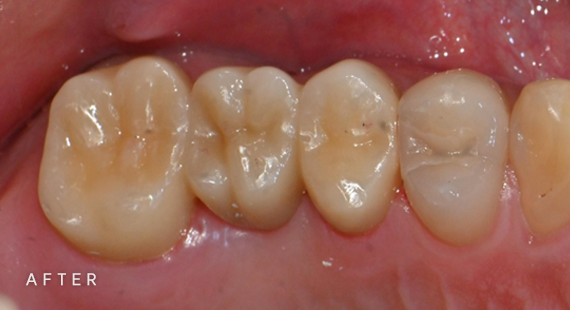

충치치료